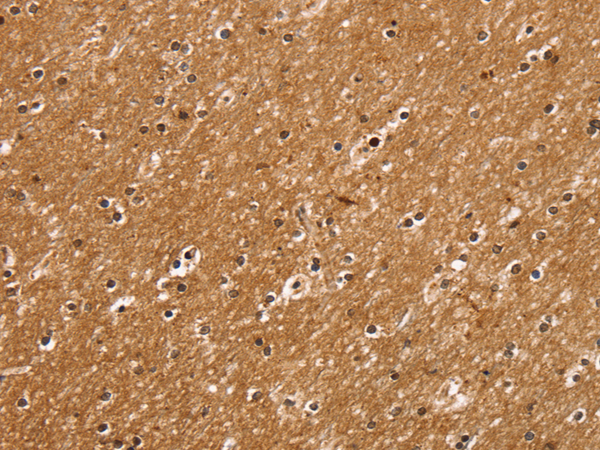

ELISA, IHC

IHC positive control:

Human brain

IHC Recommend dilution:

25-100